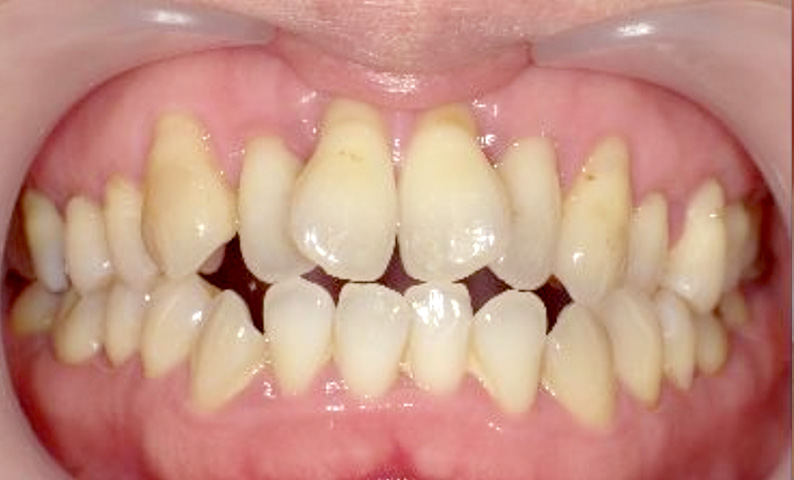

症例_003 下顎だけの部分矯正

治療期間:10ヶ月金額:24万円+税女性前歯のガタガタ下の前歯だけ上顎は補綴治療中

| Before | After |